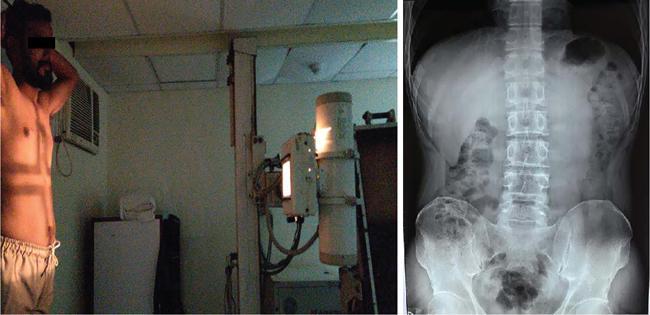

UNDERSTANDING THE ADULT ABDOMINAL RADIOGRAPH: TECHNIQUES AND INTERPRETATION Tanvi Modi Radiography of the abdomen is a common practice for the evaluation of abdominal organs. The anatomy and pathology of digestive, hepatobiliary and genitourinary systems can be assessed using radiographs, either as a stand-alone practice or as a primary imaging modality followed by contrast studies, ultrasound or cross-sectional imaging. In addition, abnormalities of the musculoskeletal or integumentary system can also be deduced on the basis of abdominal radiographs. This chapter intends to give an overview on the techniques and positioning in abdominal radiography as well as interpretation of normal and abnormal features. While superior imaging modalities such as ultrasound, computed tomography (CT), magnetic resonance imaging, capsule endoscopy and the likes have taken over abdominal imaging by and large, radiography still holds a pivotal role in certain situations and conditions, such as: The standard abdominal radiograph is taken in supine position and anteroposterior projection. This is also popularly known as the KUB (kidneys-ureters-bladder) radiograph. Previously, supine as well as erect radiographs were performed in all patients; however, this is not commonly done due to high-radiation dose. For all indications of abdominal radiography, including acute abdomen, supine radiographs are sufficient in terms of radiographic diagnosis, with the exception of perforation for which an erect chest or lateral decubitus radiograph can be performed if there is clinical suspicion. Patient should lie supine on the imaging table with median sagittal plane at right angles to the table and coincident with the midline of the table (Fig. 7.1.1.1). The body is divided into equal right and left halves by the median sagittal which passes through the sagittal suture of the skull. Pelvis should be adjusted so that the anterior superior iliac spines are equidistant from the table top. Gonadal shields, in the case of male patients, should be placed with the upper edge of the shield at the level of pubic symphysis. Although rarely used for female patients, these should be positioned between the anterior superior iliac spines and the pubic symphysis. The centre point of the image receptor should be approximately located at a point 1 cm below the line joining the iliac crests. The X-ray beam should be in a vertical direction, perpendicular to the table top and image receptor at the centre point. Collimation should be such that the soft tissue and subcutaneous region along lateral aspects of the abdominal cavity should be covered within the image. Also, the superior extent involving diaphragm and inferior extent involving the inferior pubic rami is important to look for any lower chest pathologies or any inguinal hernia. 35 × 43 cm (14 × 17 inches) in portrait orientation. On an average, abdominal radiograph exposes a patient to a dose of approximately 1.5 mSv, which is equivalent to 75 chest radiographs or 1/6th dose of a standard CT of the abdomen. The entrance skin dose is approximated to be 4 mGy. At such an effective dose, the additional lifetime risk of fatal cancer is 1 in 30,000. The exposure time is kept short. Patient is asked to exhale completely and hold their breath, with exposure taken at this point of full expiration to ensure imaging of abdominal organs in their natural positions. Modifications of this technique can be made depending on patient habitus and clinical condition. Kilovoltage peak (kVp) should be set to allow adequate visualization of abdominal soft tissue structures as well as semiopaque renal and biliary calculi. Average kVp is set at 70–85 kV. 102 cm (40 inches) Grids are commonly used to reduce scatter radiation. Placement of side marker on the image receptor at the time of radiographic exposure is essential. Bowel pattern depiction should be such that there is minimal lack of sharpness. Standard guidelines for abdominal radiography dictate that the radiograph should extend from the diaphragm up to the level of inferior pubic rami and must include the lateral abdominal wall musculature. The abdomen is divided into four quadrants on the basis of two perpendicular lines (Fig. 7.1.1.7). The vertical line passes through the mid sagittal plane and crosses the umbilicus and symphysis pubis. The horizontal line is a transverse line across the umbilicus at 90 degrees to the vertical line and is situated at the level of L4–L5 intervertebral disc. The quadrants are as follows: Another division system is dividing the abdominopelvic cavity into nine regions using two vertical and two horizontal planes (Fig. 7.1.1.8). The vertical planes, also known as the right and left lateral planes, are parallel to the midsagittal plane between midline and anterosuperior iliac spines on either side. Of the two horizontal planes, the upper transpyloric plane is at the level of lower border of L1 and the lower transtubercular plane is at the level of L5. The nine regions are: On a standard radiograph, the exposure should be such that the stomach, bowel loops, outlines of liver, spleen, kidneys, psoas muscles should be well identified. Also, lumbar transverse processes should be seen. Arch of the pubic symphysis should be visible to evaluate bladder region. A well-centred film without rotation will demonstrate bilaterally symmetrical lower ribs, iliac wings, ischial spines and obturator foramina. Different structures seen on an abdominal radiograph can be classified into five basic densities: Identification of different structures depends on the relative degree of contrast between their densities. The demarcation is clearer in chest and is diminished in abdomen due to relative similar soft tissue density of various structures. On a normal radiograph, relatively large amounts of gas in stomach and colon with minimal small bowel gas can be seen. Further, colonic gas can vary from negligible to extensive, mimicking obstruction pattern; however, usually the gas is enough to delineate colonic haustral pattern. Faecal matter gives a mottled appearance to colonic gas. Short-air fluid levels on an erect radiograph may be seen even in normal cases. The normal appearance of small bowel loops on an abdominal radiograph follows the rule of threes: Stomach is seen in the left upper quadrant and is visualized when distended with air. It is commonly seen extending from T11 to L2 level. Common feature identifying the stomach is the fundal gas which is usually seen as an air fluid level within the gastric lumen. Small bowel loops are distributed to the centre of the abdominal cavity and large bowel loops are peripheral. Duodenum is predominantly situated in right upper quadrant. It extends to left upper quadrant in the region of duodenojejunal flexure. Jejunum occupies the left upper and lower quadrants and is easily identified due to the presence of thick, numerous, closely spaced valvulae conniventes (Fig. 7.1.1.9A). The ileum occupies both lower quadrants and extends into right upper quadrant. Ileum has few and less prominent valvulae as compared to jejunum (Fig. 7.1.1.9B). Ascending and descending colon are retroperitoneal and have relatively fixed positions along lateral aspect of the abdominal cavity on either side. Transverse and sigmoid colon, on the other hand, may have a variable position due to their mobility along mesocolon and redundant pattern. These can be identified with confidence on account of haustrations and faecal matter (Fig. 7.1.1.10). Haustrations are usually well seen in ascending and transverse colon and poorly delineated beyond splenic flexure. Caecum is in the right lower quadrant, though it may be mobile or pulled up. Rectal gas is usually seen in the midline at the level of pelvis and its presence rules out large bowel obstruction. All these positions may vary due to anatomical conditions such as malrotation or pathological conditions, for example volvulus. Liver, spleen and renal outlines cannot be completely traced with precision due to the overlap by bowel loops. On a frontal projection, the liver appears as a triangular structure occupying right and left hypochondrium and epigastric region. Occasionally, the right lobe may be seen extending lower than the right renal shadow. This is a normal variant known as Reidel’s lobe. Gall bladder is situated in the posterior and inferior region of the liver and any pathology of the gall bladder should be looked for in this region. On a lateral radiograph, the gall bladder is anterior to the midcoronal plane. This helps in distinguishing gall bladder calculi from renal calculi, which will be more posteriorly situated. Spleen is seen in left upper quadrant/left hypochondrium, flushed to left lower ribs and left hemidiaphragm. Pancreas is present in the epigastric region (right and left upper quadrants) and is usually not identified in the absence of a pathology. The kidneys are bean-shaped retroperitoneal organs which are seen on either side of the vertebral column and lateral to psoas muscles. Due to the presence of liver on the right side, this kidney is slightly lower in position as compared to its contralateral counterpart. The visualization of kidneys on radiographs is facilitated by the surrounding fatty capsule. Kidneys lie between T11–12 and L2 level, with left kidney 1 cm higher than the right. Psoas muscle shadow can be normally seen along lateral aspect of lumbar spine bilaterally and is mildly concave (Fig. 7.1.1.11). Abdominal wall muscles are not routinely assessed on radiography; however, inclusion of lateral abdominal wall (muscles as well as subcutaneous plane) is a must while performing radiography. The flank stripe or the properitoneal fat stripe is a fat density linear concavity seen along lateral abdominal wall (Fig. 7.1.1.11). It is bound by the paracolic gutters and air-filled ascending and descending colon. All the solid organs in the abdomen are identified due to the fat density outlining them. Distortion of these fat lines helps in identifying organomegaly or focal mass lesions. The dome of urinary bladder is outlined by fat, which aids in differentiating its density from other soft tissue structures of the pelvis. Not all calcifications seen on abdominal radiograph are abnormal. Some may depict age-related changes such as vascular calcifications involving abdominal aorta, pelvic vessels, splenic artery in the region of left upper quadrant. Within the pelvis, phleboliths may be seen and mistaken for urinary calculi. Assessment of lumbosacral spine, iliac bones and femoral heads can be made on the basis of plain radiography. Degenerative changes may be commonly seen. Lower ribs can also be evaluated for pathologies. Dilated small bowel loops with rounded soft tissue density in midline over umbilical region suggests obstruction secondary to umbilical hernia. Pneumoperitoneum must be looked for in all cases of acute abdomen. While erect chest and left lateral decubitus radiographs can detect even 1 mL of free air, there are multiple signs on supine radiograph to suggest this diagnosis, for example Rigler’s sign, falciform ligament sign, football sign (Figs. 7.1.1.24 and 7.1.1.25). Retroperitoneal perforation may demonstrate air outlining psoas muscles and retroperitoneal organs. Small amount of free air may persist in the abdominal cavity up to 3 weeks after surgery, although it usually resolves within a week. Clinical history is important in such cases. Air foci within the bowel wall may represent bowel ischaemia/strangulation. Linear gas patterns in right hypochondrium may be due to two causes, that is pneumobilia and pneumoporta. The former can be seen normally postbiliary surgery, sphincterotomy, ERCP or in the case of abnormal fistulous communication between bowel and biliary tree (Fig. 7.1.1.26A). Pneumoporta (Fig. 7.1.1.26B) is a red flag and warrants further investigation to look for conditions such as mesenteric ischaemia and toxic megacolon. Pneumobilia is more centrally located whereas air shadows in pneumoporta are seen reaching up to periphery of liver. Air foci over renal shadows (Fig. 7.1.1.27), gall bladder or pancreas, in the absence of recent procedural history, suggest fulminant infection and mandate urgent intervention. Central midline calcific foci between T9 and T12 vertebrae can be attributed to calcific pancreatitis (Fig. 7.1.1.28). In the left upper quadrant, areas of calcification seen involving a shrunken spleen may be seen in autosplenectomy. In right upper quadrant, calcified gall stones may be seen. These tend to be small, multiple, uniformly circumscribed and ring-like in appearance with central translucency (Fig. 7.1.1.29A). Mercedes Benz sign, a triradiate pattern of gas lucency, is associated with gallstones. In contrast, renal calculi are more commonly solitary, irregular, of homogenous density, conform to renal calyceal or pelvic outline (Fig. 7.1.1.29B) and are sometimes of staghorn configuration. On lateral view, the gall stones are more anteriorly located as compared to renal calculi, which may be partly superimposed on lumbar vertebrae. Ureteric calculi tend to overlap bony structures such as lumbar transverse processes (Fig. 7.1.1.29B) or sacroiliac joints. Extensive or patchy, curvilinear calcification of gall bladder wall is known as porcelain gall bladder which is often associated with malignant transformation. Calcification involving adrenal glands may be secondary to infection or haematoma, or a congenital condition known as Wolman’s disease where there is bilateral involvement. Discontinuous discrete midline tram track calcification in the abdomen may indicate atherosclerotic changes in abdominal aorta and branch vessels. However, when the calcification is in a globular pattern and seen below the level of L2 vertebra, aortic aneurysm should be suspected (Fig. 7.1.1.30). Appendicoliths, though not commonly seen, may sometimes be detected in right iliac region. Pelvic calcifications: vesical calculi, distal ureteric or vesicoureteric junction calculi, calcified fibroids, ovarian dermoid with tooth-like calcifications (Fig. 7.1.1.31) may be the cause of abdominal pain and should be diligently looked for. Vesical calculi are usually more large and central in location whereas calcification due to fibroids may be more lateral. Schistosomiasis is another cause of bladder wall calcification, as is calcification of bladder tumours. Phleboliths tend to be bilaterally symmetrical, with a lucent centre unlike ureteric calculi. While it is believed that phleboliths are located below the level of ischial spines and ureteric calculi above, this is not always true and should be confirmed with CT. Fluid may collect adjacent to properitoneal fat line, forming a linear soft tissue density separating the fat line from the ascending or descending colon. Hellmer’s sign demonstrates medial displacement of lateral edge of liver (hepatic angle), due to fluid collection or ascites. Gross ascites may appear as generalized abdominal haziness or diffuse increased density of pelvis. Abscesses can involve any solid organ and in such cases may be difficult to demonstrate on plain radiography alone. Enlargement of organ or faint gas densities within can be suggestive of the same. In the case of peritoneal abscess, mottled density due to air, fluid and necrotic contents point towards this diagnosis, especially in right iliac fossa in association with appendicitis. Retroperitoneal abscess, similar to any retroperitoneal mass, may cause displacement of retroperitoneal structures (Fig. 7.1.1.32). Subdiaphragmatic abscesses may show concomitant ipsilateral pleural effusion (Fig. 7.1.1.33). These should be differentiated from Chilaiditi syndrome. Fluid and soft tissue lesions present with the same density on radiographs. While it is difficult to characterize the lesion and organ of origin, clues for the same can be provided by organomegaly (Fig. 7.1.1.34), distortion of fat surrounding solid organs, displacement of bowel loops or solid organs. For example, a retroperitoneal lesion may cause anterior or inferior displacement of kidney, a pelvic mass may cause upward displacement of small bowel loops. Different densities such as fat or calcification may help in identifying organ of origin (e.g. fat and tooth densities seen in ovarian dermoid). Convexity of margins of psoas muscle on an abdominal radiograph can be due to haematoma, abscess or intramuscular tumour. Radiographs are performed for the initial diagnosis of foreign body in the abdomen including type, number of foreign bodies, location, size and shape (Fig. 7.1.1.35). Radiolucent foreign bodies such as wood, plastic, chicken bones will not be easily identified on radiography. Low kVp (65–70 kVp) can increase contrast and help identify these objects. In addition to an abdominal radiograph, chest radiography is also performed to exclude aspiration or oesophageal location of foreign body. Ingested or introduced foreign bodies may cause complications such as obstruction, perforation, fistula formation and sepsis. Hence, once their presence is confirmed, follow up radiography must be performed until they are eliminated. One must look for fractures/dislocation injuries involving the vertebrae or pelvic bones, especially after history of trauma. Lucent expansile lesions or sclerotic bony deposits which represent neoplasms, absent pedicle sign in cases of metastasis, metabolic bony changes such as rugger jersey appearance, Paget’s disease, arthropathies such as ankylosing spondylitis with bamboo spine appearance and sacroiliitis (Fig. 7.1.1.36) are some of the conditions which may be diagnosed based on an abdominal radiograph. Overlap of bowel loops over iliac blades may lead to a misdiagnosis of lucent lesions and should be evaluated with caution. Basal pneumonia may be the cause of acute abdominal pain and should be looked for in abdominal radiography. Similarly, pleural effusion, pericardial effusion, calcified pleural plaques, achalasia, interstitial fibrosis are few other findings that can be seen in lower chest on an abdominal radiograph. Basilar atelectasis can give a deceptive appearance of pneumoperitoneum (Fig. 7.1.1.37). Surgical clips, commonly in right hypochondrium after cholecystectomy, drainage tubes, ventriculoperitoneal shunts, femoral line catheters, IVC filters, stents (vascular, renal, biliary) (Fig. 7.1.1.38), stoma bags, contraceptive devices are some structures that may be seen in an abdominal radiograph. Correct knowledge of patient history and normal locations of these structures prevents misdiagnosis. Certain artefacts may be projected upon the radiograph due to surface structures such as trouser buttons, body piercing, sequins over clothing and should not be considered as a pathology. Multiple skin surface nodules in cases of neurofibromatosis, soft tissue focal swellings, such as abscesses, lipomas, haematomas, desmoid tumours and malignant lesions may be incidentally seen on radiography. These can be further evaluated using ultrasound or CT. Subcutaneous emphysema is another finding that may be seen in lower abdominal wall secondary to retroperitoneal perforation or diffusely along abdominal wall in the case of bowel perforation (Fig. 7.1.1.39). Foreign bodies such as bullets and pins may be seen lodged in abdominal wall. A systematic approach to abdominal radiographs is important for accurate diagnosis as follows: Despite the development of newer techniques for imaging of the abdomen, plain radiography still holds an important place in the initial assessment of acute abdomen. Positive and negative findings on an abdominal radiograph can direct further investigation. Ideal positioning, recognition of normal appearances and keen scrutiny for pathologies is a sine qua non for radiologists reading a plain film of the abdomen. OESOPHAGOGRAM Padma V. Badhe, Vikram Reddy, Sultan Moinuddin Shaukatali, Zillani Alam, Ravi Varma, Abhishek Bairy, Dasari Ravikiran, Revati Tekwani, Soniya Patankar, Megha Nair, Gautham Shankar Oesophagogram is the process of obtaining radiological images and simultaneous motion recording to evaluate function and disorders of pharynx, oesophagus and proximal stomach. Oesophagogram is usually done primarily to evaluate dysphagia. Some of the common indications are oesophageal motility disorders, strictures, gastro-oesophageal reflux disease (GERD) and suspected masses. It can also be used to detect uncommon anomalies like vascular rings/slings and aberrant anatomy. It also helps to evaluate further in cases where there is inability to pass upper GI scope. Double-contrast oesophagogram is mainly indicated in early mucosal disease like erosion, polyp, infection and tumours. If a motility disorder is suspected, dynamic technique (e.g. videofluoroscopy) is used for dysphagia or aspirations in cases of stroke, neuromuscular disorders, post head and neck surgery or radiation. Barium oesophagogram is contraindicated in suspected cases of perforation and tracheoesophageal fistula, aspiration, rarely if there is hypersensitivity to barium suspensions. It is also contraindicated in suspected oesophageal perforation where a water-soluble contrast agent is more suitable. However, ionic water-soluble contrast agent is better avoided in cases of aspiration or fistula with airway. The contrast examination of the pharynx is dangerous in cases of acute epiglottitis and must be ruled out on plain radiograph. An 80% w/v barium suspension is used in full column views. However, 200%–250% w/v barium suspensions is usually required for mucosal relief films. The barium sulphate mixture is fed to the patient either by spoon, by glass, or through a drinking straw, depending on its consistency. In videofluoroscopy, the pharyngeal phase of swallowing is usually safer with barium pudding than with thick barium and safer with thick barium than with thin barium. However, if the major abnormality is poor pharyngeal contraction leading to stasis in the piriform sinus (and epiglottic tilt is normal), a thin liquid is safer. Epiglottic motility is better assessed with thin barium because thick barium often obscures the epiglottic tip. Fluoroscopic equipment capable of cine fluoroscopy and capability for rapid sequence spot images (high frame rate) is needed for this examination, Barium suspension, straw, glass, Lead apron and radiation protective equipment. The patients are instructed to fast after midnight before the day of the examination. The pharynx should be made as dry as possible during the examination as high-density barium adheres to dry pharyngeal mucosa. Activities like smoking, chewing gum and lozenges must be abstained before the procedure as they impair barium coating by increasing the salivary secretion. Regular oral medications must be taken with sips of water; however, insulin must be skipped on the morning of examination. The major principles of a good oesophagogram includes mucosal coating, distension and projection. A routine oesophagogram consists of screening of the oral, pharyngeal and oesophageal phases of swallowing, single and double-contrast examination of pharynx, single contrast, double-contrast and mucosal relief views of the oesophagus. In cases of dysphagia, the examination is tailored depending on whether the symptoms are either pharyngeal or oesophageal and initial fluoroscopic findings. If patients’ symptoms are suggestive of oral or pharyngeal disorder then pharynx is evaluated first. Similarly, if patient is suspected to have thoracic oesophageal disease then, double-contrast examination of the oesophagus is performed before the pharyngeal evaluation. During an oesophagogram the positioning of the patient varies according to the type of examination (Table 7.1.2.1).